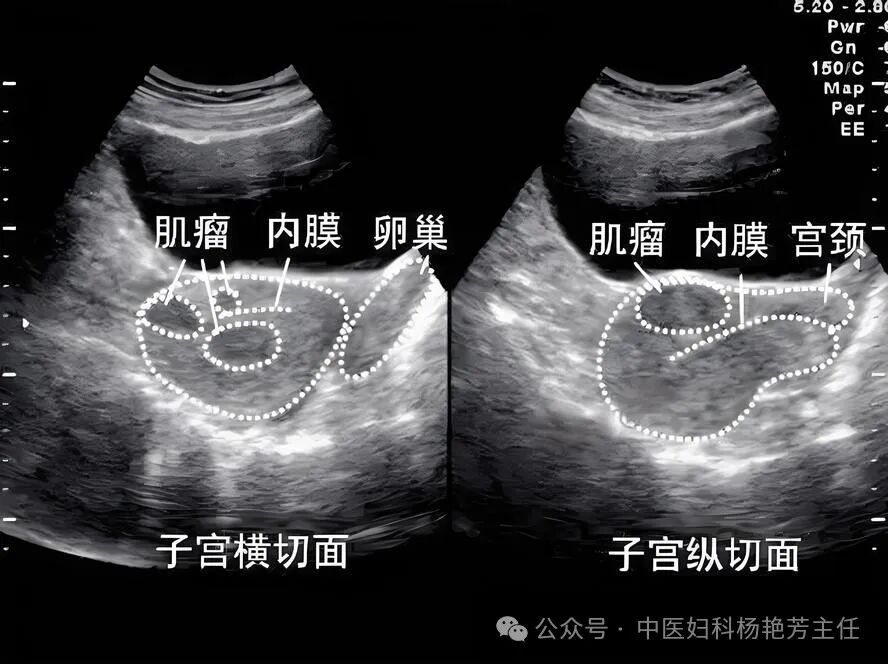

一位患者因多发性肌瘤结节而感到不安,最近又诊断出乳腺囊肿,这让她意识到情况可能比较严重。这些结节已经存在了相当长的时间,并且情况复杂。

然而,现在她又发现了乳腺囊肿,这让她感到担忧。尽管这个囊肿相对较小,她在就诊前进行了彩超检查,结果显示囊肿大约0.8毫米。此外,她的月经周期也不规律,这大大小小的一堆问题了,她觉得不能等了。